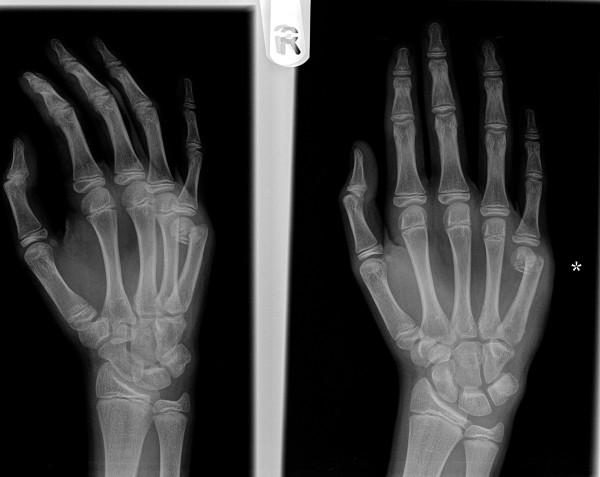

We reviewed our results and complications of using a pre-bent 1.6 mm Kirschner wire (K-wire) for extra-articular metacarpal fractures. The surgical procedure was indicated for angulation at the fracture site in a true lateral radiograph of at least 30 degrees and/or in the presence of a rotatory deformity.

A single K-wire is pre-bent in a lazy-S fashion with a sharp bend at approximately 5 millimeters and a longer smooth curve bent in the opposite direction. An initial entry point is made at the base of the metacarpal using a 2.5 mm drill by hand. The K-wire is inserted blunt end first in an antegrade manner and the fracture reduced as the wire is passed across the fracture site. With the wire acting as three-point fixation, early mobilisation is commenced at the metacarpo-phalangeal joint in a Futuro hand splint. The wire is usually removed with pliers post-operatively at four weeks in the fracture clinic.

We studied internal fixation of 18 little finger and 2 ring finger metacarpal fractures from November 2007 to August 2009. The average age of the cohort was 25 years with 3 women and 17 men. The predominant mechanism was a punch injury with 5 diaphyseal and 15 metacarpal neck fractures. The time to surgical intervention was a mean 13 days (range 4 to 28 days). All fractures proceeded to bony union. The wire was extracted at an average of 4.4 weeks (range three to six weeks). At an average follow up of 8 weeks, one fracture had to be revised for failed fixation and three superficial wound infections needed antibiotic treatment.